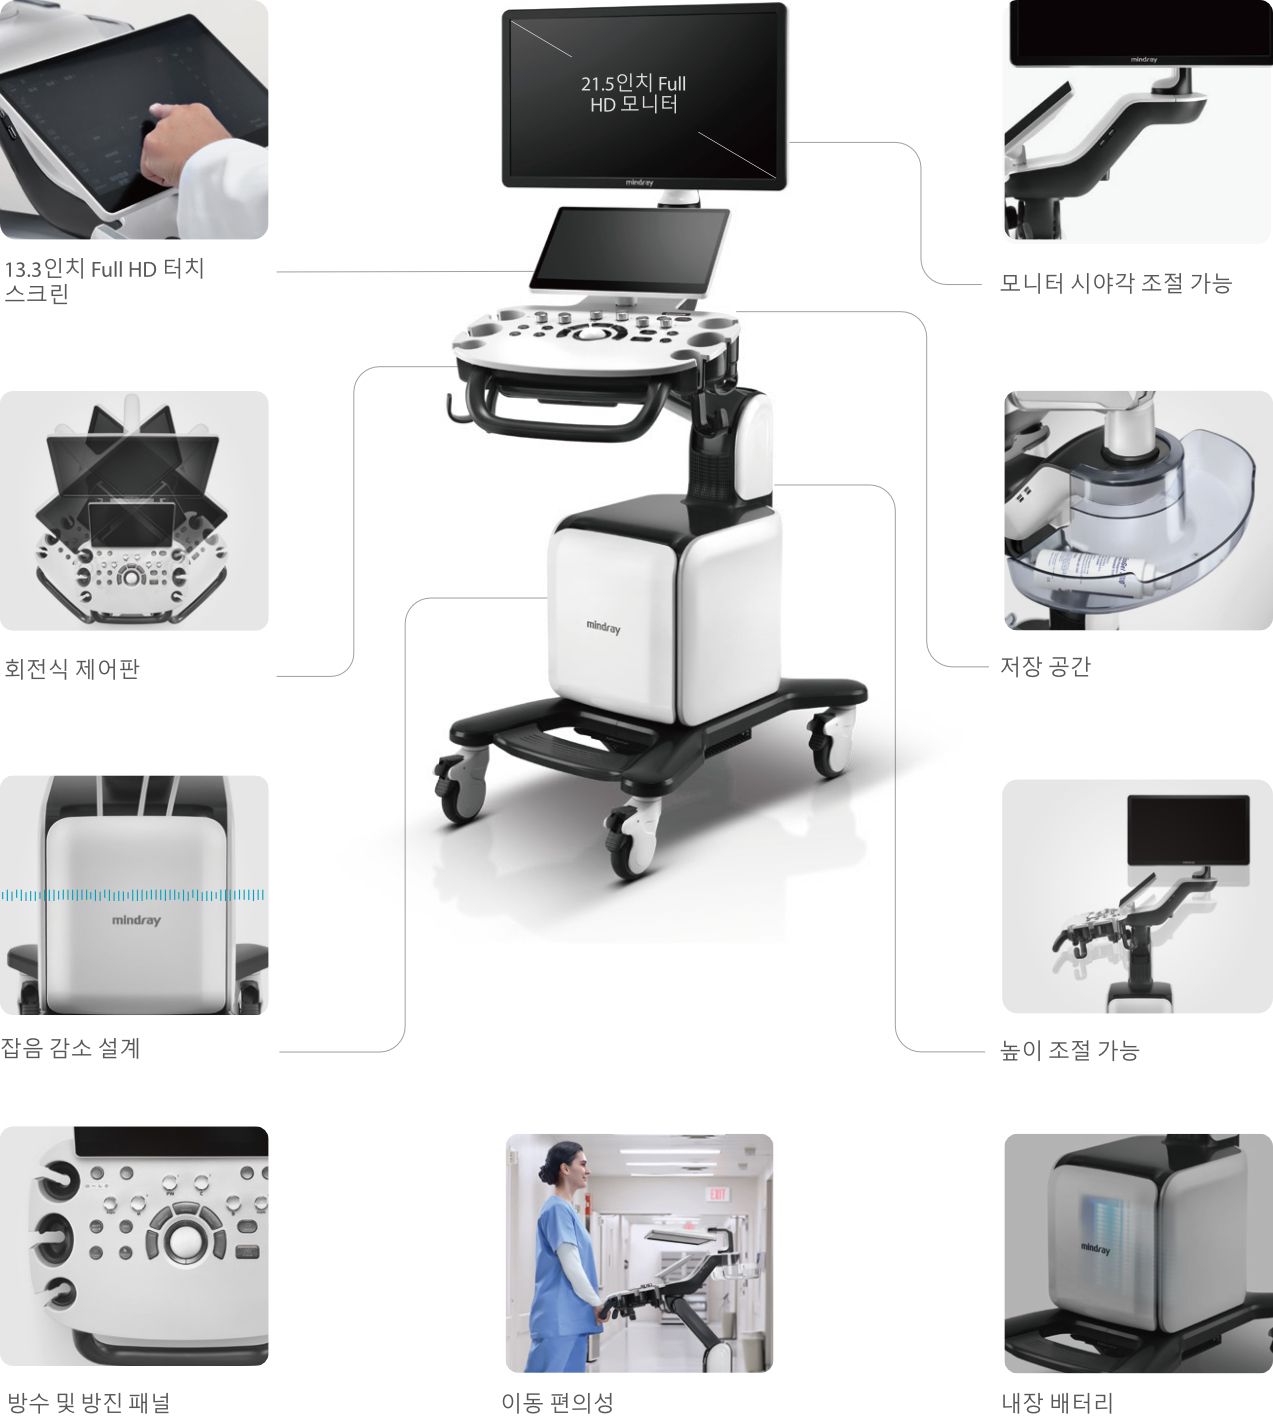

??? ??? ???

Consona? ???? ??? ??? ?? ??? ??? ????? ??? ? ?? ??? ???? ???? ?????.

???, ??, ?? ?? ?, ?? ?? ?? ?? ??? ?? ???? ?? ?? ? ???? ???? ???? ?? ??? ??? ?????.